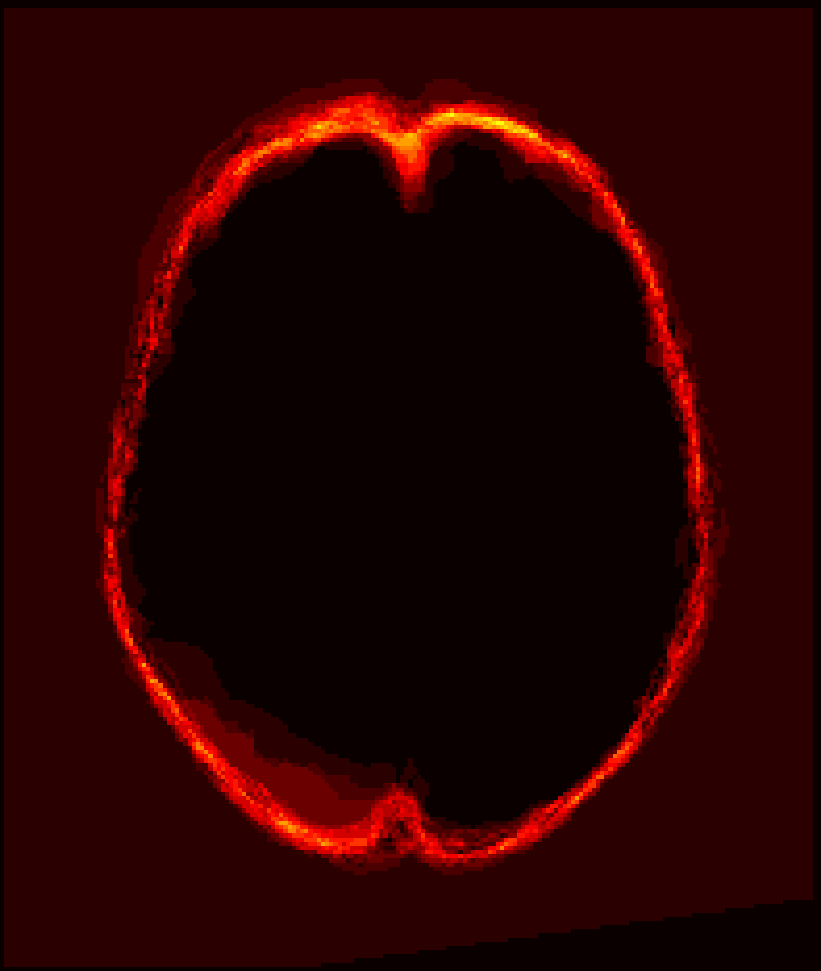

Fig. 1 shows example images from each dataset to illustrate image variability. IBSR and LPBA40 contain images from normal subjects and include large portions of the neck; BRATS has very low out-of-plane resolution; and the TBI dataset contains large pathologies and abnormal skulls.

Refer to caption

Figure 1: Illustration of image appearance variability on a selection of images from each (evaluation) database. From top to bottom: IBSR, LPBA40, BRATS and TBI.